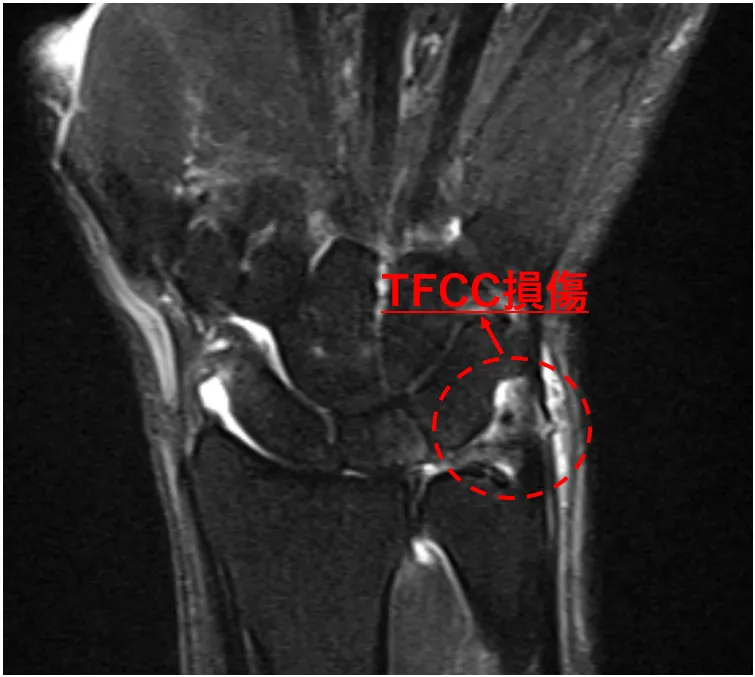

右TFCC損傷

MRI所見ではTFCC損傷を認めました。